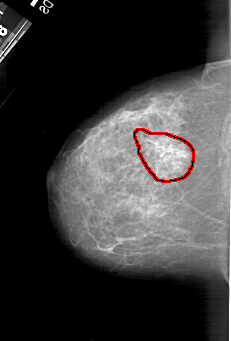

A_1217_1.LEFT_MLO

FILE: A_1217_1.LEFT_MLO.OVERLAY

TOTAL_ABNORMALITIES 1

ABNORMALITY 1

LESION_TYPE MASS SHAPE ARCHITECTURAL_DISTORTION MARGINS SPICULATED

ASSESSMENT 4

SUBTLETY 2

PATHOLOGY MALIGNANT

TOTAL_OUTLINES 1

BOUNDARY